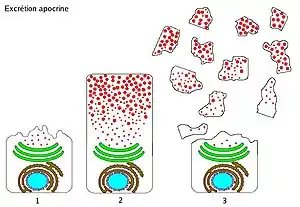

| Apocrine – by membrane budding (loss of cytoplasm) |

Apocrine (/ˈæpəkrɪn/)[1] is a term used to classify the mode of secretion of exocrine glands. In apocrine secretion, secretory cells accumulate material at their apical ends, and this material then buds off from the cells, forming extracellular vesicles. The secretory cells therefore lose part of their cytoplasm in the process of secretion.

Apocrine secretion is less damaging to the gland than holocrine secretion (which destroys a cell) but more damaging than merocrine secretion (exocytosis).